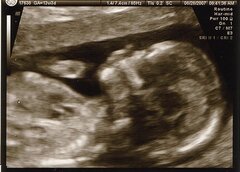

Le fœtus pourrait ressentir la douleur dès la 13ème semaine de grossesse

Une étude scientifique récente montre que le foetus pourrait ressentir la douleur dès le quatrième mois de la grossesse. Mis en avant dans l'article de deux scientifiques publié par le Journal of Medical Ethics, ces résultats viennent ainsi bouleverser l'idée couramment reçue selon laquelle un foetus ne pourrait sentir la douleur qu'à partir de la 24 semaine de gestation, et par conséquent ne souffrirait pas de l'avortement jusqu'à ce stade.

Jusqu'à présent, la plupart des études affirmait que la perception de la douleur dépendait du cortex cérébral et des liaisons entre le cortex et le thalamus, qui ne deviennent fonctionnelles qu'après 24 semaines de gestation. De nouveaux résultats ont démontré que l'épreuve de la douleur n'était pas nécessairement liée au fonctionnement du cortex : "Même si on considère le cortex nécessaire à l'expérience de la douleur, il y a maintenant assez de preuve que les projections thalamiques (ndlr: informations sensitives) dans la sous-plaque, qui surviennent autour des 12 semaines de gestation, sont fonctionnelles et équivalents aux projections thalamocorticales qui apparaissent autour des 24 semaines de gestation". Il est donc scientifiquement probable que le foetus perçoive la douleur dès sa 13ème semaine de gestation.

Crédit photo : Cody - Creative Commons